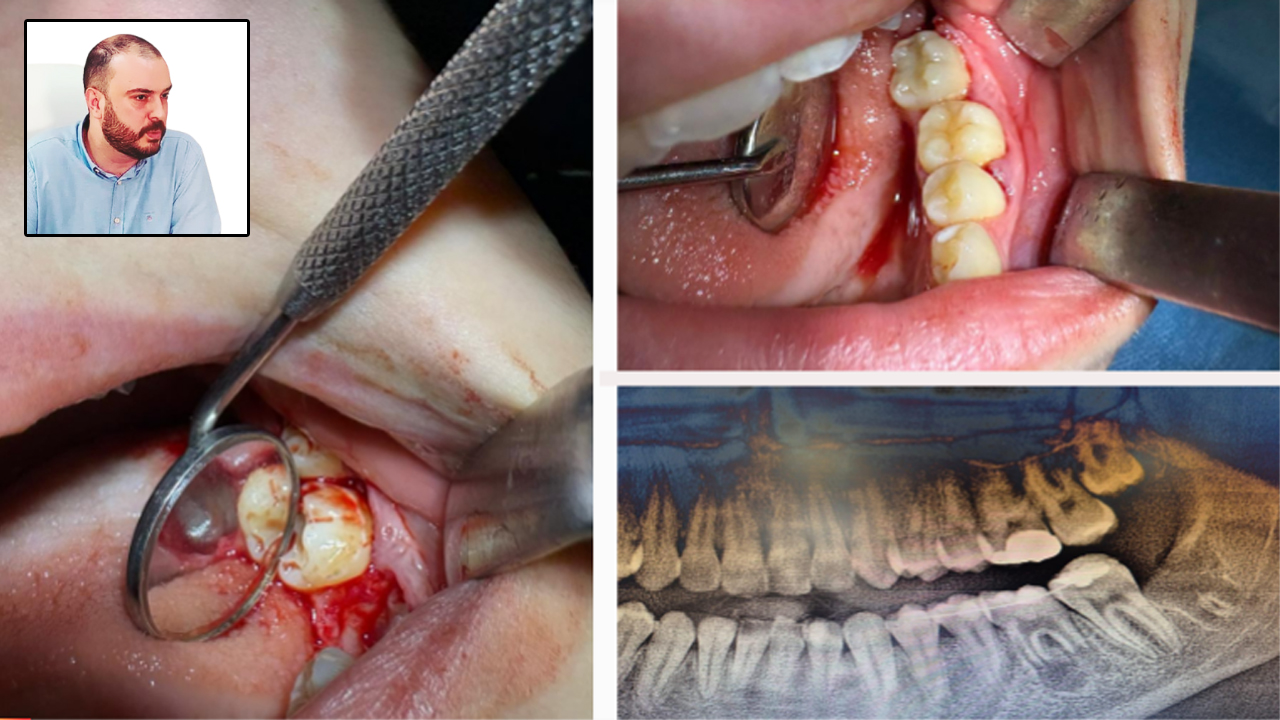

Karabük Ağız ve Diş Sağlığı Eğitim ve Araştırma Hastanesi’nde, 16 yaşındaki bir hastaya diş kaybına karşı doğal ve etkili bir çözüm olan “diş ototransplantasyonu” yöntemi başarıyla uygulandı.

Edinilen bilgilere göre; Genç hastanın ileri düzey çürük nedeniyle tedavi amaçlı olarak bir daimi azı dişi çekildi. Ancak çocuk yaşta çene gelişimi devam ettiği için implant uygulaması gibi klasik tedavi yöntemleri uygun görülmedi. Bu nedenle hastanın kendi ağzında kemik içinde gömülü halde bulunan üçüncü azı dişi (yirmi yaş dişi), uzman ekip tarafından operasyon mikroskobu eşliğinde cerrahi operasyonla çıkarıldı ve hazırlanan yuvaya nakledildi. Ayrıca, dişin daha sağlıklı bir şekilde iyileşebilmesi için çocuğun kendi kanından elde edilen PRF (kişinin kendi kanından elde edilen, hücre yenilenmesini destekleyen doğal bir biyomateryal) nakil işlemi öncesinde hazırlanan yuvaya konuldu.

Karabük ADSEAH Başhekimi Prof. Dr. Ahmet Taylan Çebi, konuyla ilgili olarak  ”Bu özel işlem, hastanın kendi dişi kullanıldığı için hem doğal görünüm hem de fonksiyon açısından büyük avantaj sağlamaktadır. Dişin vücut tarafından kabul edilme ihtimali yüksek olduğu için uzun vadeli başarı oranları da oldukça yüksektir. Hastanın tedavisi, Endodonti Anabilim Dalı öğretim üyesi Doç. Dr. Olcay Özdemir ile Ağız, Diş ve Çene Cerrahisi Anabilim Dalı öğretim üyesi Dr. Öğr. Üyesi Muhammed Abdullah Çege tarafından başarılı bir şekilde gerçekleştirilmiştir.” dedi.